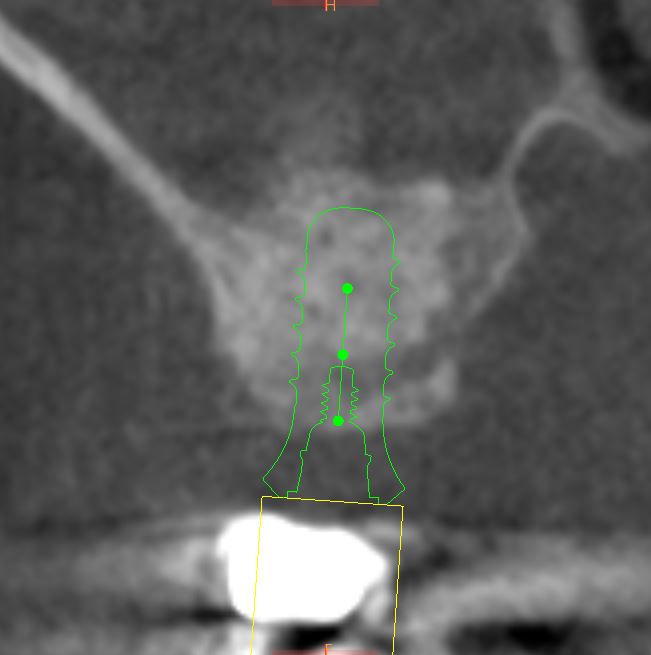

Le sinus lift (accès par voie latérale) : lorsqu’il manque de l’os en arrière du maxillaire supérieur, on accède au sinus par une paroi latérale et on le comble avec nos matériaux. Cela augmente la hauteur osseuse disponible.

Le push-back (apport par voie crestale) : cette méthode permet d’apporter de l’os par le trou de forage lors de la pose de l’implant.